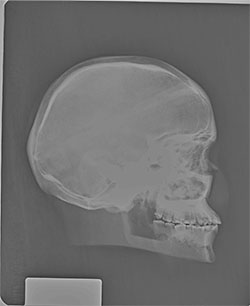

BREAK-APART PIXY Skull X-Ray BREAK-APART PIXY Ankle & Foot X-Ray 1 BREAK-APART PIXY Ankle & Foot X-Ray 2